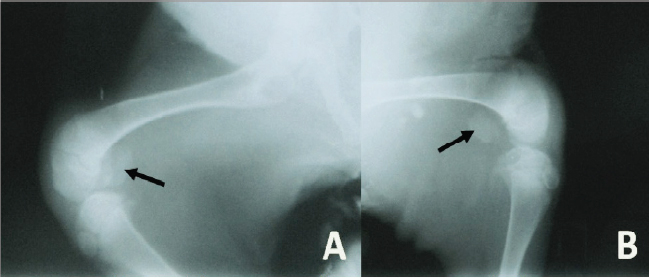

Radiographically, the stifle areas of the affected goats showed ventrocaudal PL in three cases (Figs. 2 and 3) and dorsal PL in the other two cases, for which surgical treatment was performed (Fig. 4A).

Fig. 3. Mediolateral radiograph of the right (A) and left (B) stifle of a 3-month-old goat with bilateral PLs. The radiograph shows severely ventrocaudally luxated patellae (arrows).